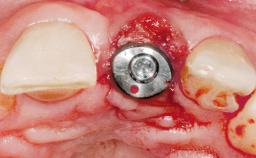

Late Placement of an Implant in a Maxillary Left Central Incisor Site

A 36-year-old female patient was referred for the replacement of the upper left central incisor (tooth 21), which had fractured. Although the tooth had been asymptomatic for many years, the crown began to loosen, at which time she presented to her dentist for an assessment. Teeth 21 and 22 had both been endodontically treated many years previously. She was a healthy individual and a non-smoker.

| Type of Implants | Two-Piece |

| Attachment | Two-Piece |